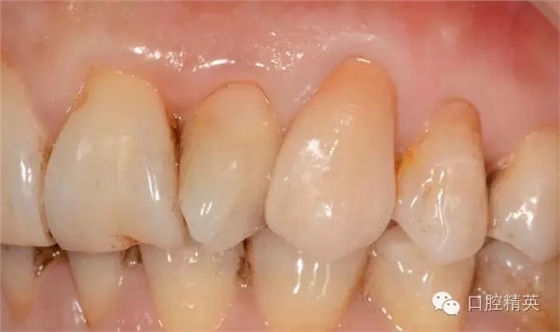

圖8修復(fù)體照片

圖9修復(fù)體代入模型照

圖10修復(fù)體代入口內(nèi)照